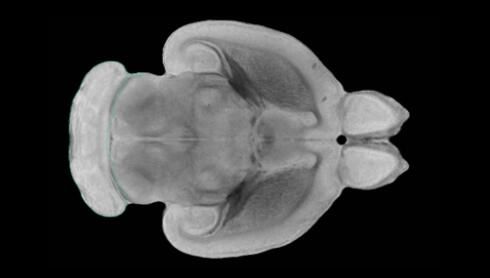

隨著機(jī)體年齡增加,肌肉和關(guān)節(jié)都會(huì)變得僵硬,這就會(huì)使得日?;顒?dòng)變得更加困難,本文研究表明,我們的大腦也是如此,與年齡相關(guān)的大腦僵硬對(duì)大腦干細(xì)胞的功能或許有著重要影響。文章中,研究人員對(duì)年輕和老化大鼠的大腦進(jìn)行研究闡明了年齡相關(guān)大腦僵硬對(duì)少突膠質(zhì)前體細(xì)胞(OPCs,oligodendrocyte progenitor cells)功能的影響。OPCs是一類對(duì)維持正常大腦功能非常重要的大腦干細(xì)胞,其對(duì)于髓磷脂的再生也非常重要,髓磷脂是神經(jīng)組織周圍的脂肪鞘,在多發(fā)性硬化癥中髓磷脂的再生常常會(huì)被損傷,機(jī)體老化對(duì)這些細(xì)胞的影響常常會(huì)誘發(fā)多發(fā)性硬化癥的發(fā)生,這些細(xì)胞的功能在老化的健康人群中同樣會(huì)下降。

為了確定老化OPCs的功能缺失是否可以被逆轉(zhuǎn),研究人員將來自老化大鼠機(jī)體的老化OPCs轉(zhuǎn)移到了年輕大鼠柔軟的海綿狀大腦組織中去,值得注意的是,這些老化的大腦細(xì)胞能夠重新恢復(fù)活力,其行為非常像年輕更加強(qiáng)壯的細(xì)胞。這項(xiàng)研究中,研究人員在實(shí)驗(yàn)室中開發(fā)出了具有可變僵硬程度的新型材料,并在受控環(huán)境下研究這些材料的生長及其對(duì)大鼠大腦干細(xì)胞的影響,這些材料能被工程化改造具有和年齡或老化大腦相似的柔軟程度。

為了深入理解大腦組織柔軟和僵硬影響細(xì)胞行為的分子機(jī)制,研究人員對(duì)細(xì)胞表面一種名為Piezo1的蛋白質(zhì)進(jìn)行了分析,該蛋白質(zhì)能“告知”細(xì)胞其周圍的環(huán)境為柔軟或僵硬。研究者Kevin Chalut說道,我們發(fā)現(xiàn),當(dāng)在僵硬材料上促進(jìn)年輕具有功能性的大鼠干細(xì)胞時(shí),這些細(xì)胞就會(huì)表現(xiàn)出功能異常,并失去其再生的能力,實(shí)際上其行為與老化細(xì)胞相似。當(dāng)將老化的大腦細(xì)胞在柔軟材料上生長時(shí),其功能就會(huì)表現(xiàn)得像年輕細(xì)胞一樣,換句話說,其能夠重新恢復(fù)年輕的活力。